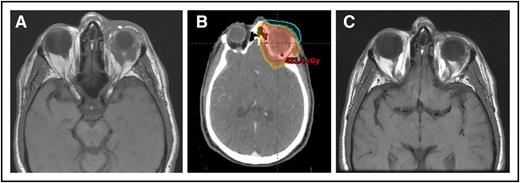

(A) A 64-year-old man with MZL of the left orbit. (B) An intensity-modulated RT plan of 24 Gy was designed, but only 4 Gy was delivered with near-CR obtained. (C) Seven months’ follow-up after only 4 Gy with no progression.

More recently, a very low dose of only 4 Gy (2 Gy ×2) was shown to be adequately effective in a prospective randomized study from the United Kingdom, and a group from Stanford reported on their favorable experience with this low-dose schedule.8,9